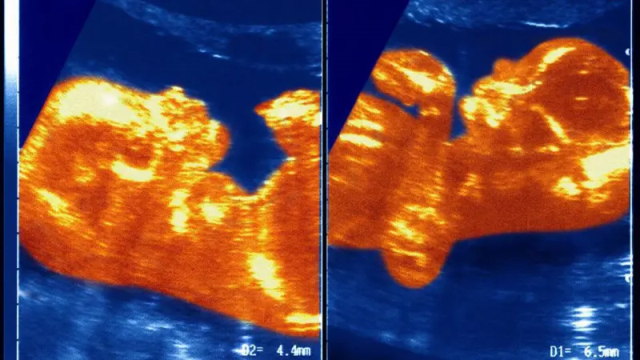

SAĞLIKLI BİR ERKEK ÇOCUK DÜNYAYA GETİRDİ

Kadınlarda XY kromozomu taşıyan vakalar genellikle doğurganlık sorunlarıyla ilişkilendirilirken, Ana Paula için durum farklıydı. Araştırma sürecinde hamile kaldı ve sağlıklı bir erkek çocuk dünyaya getirdi.

Genetik testler, bebeğin DNA'sının normal olduğunu gösterdi: kromozomların yarısı anneden, yarısı babadan geliyordu; amcadan ise hiç genetik materyal taşımıyordu.

Ana Paula için en önemli şey, bu genetik durumun hamileliğini etkilememesiydi. Paula "Bu, hedefimin önüne geçebilecek bir şey değildi. Hedefim bebeğimi doğurmaktı" dedi.